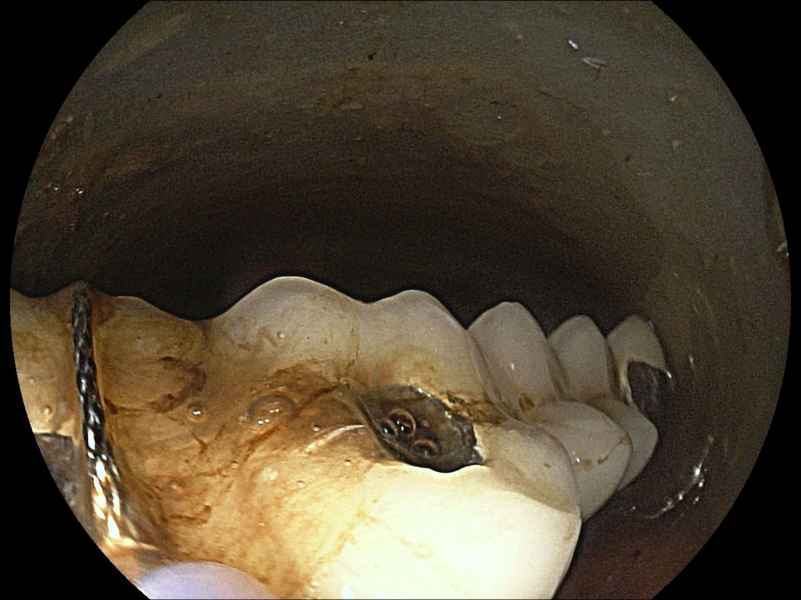

Infinity stones in a choledochocele